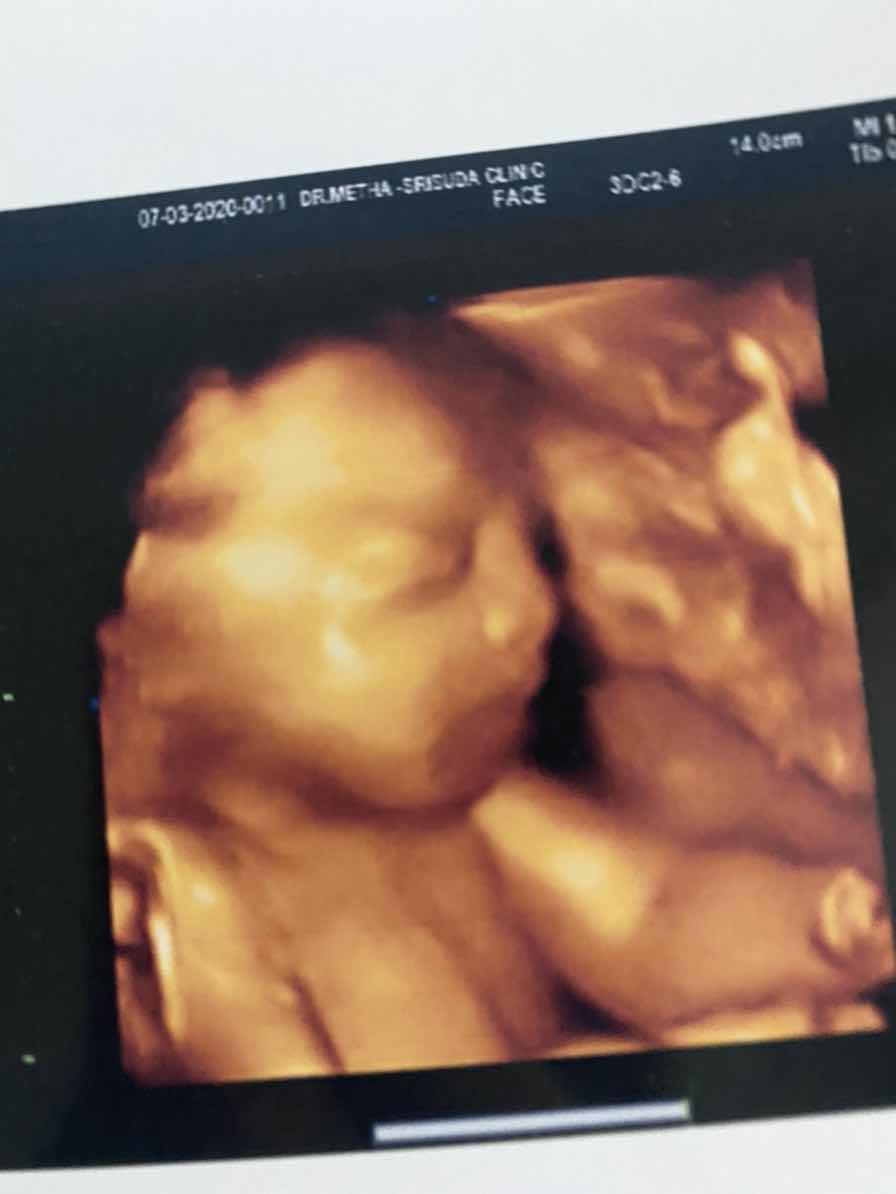

28wค่ะลูกสาว